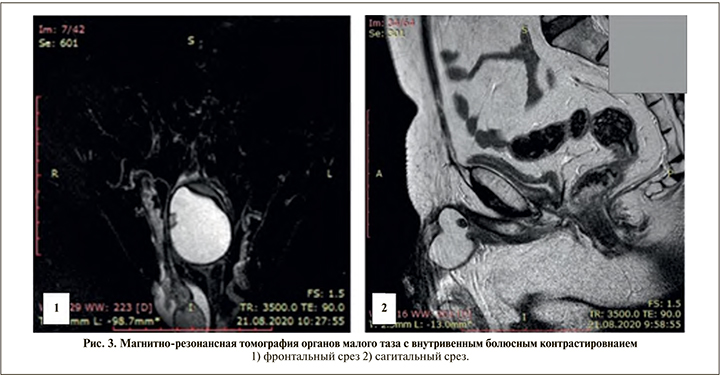

В основании полового члена парамедианно - несколько больше справа - определяется объемное кистозное образование овальной формы с четкими ровными и слегка волнистыми контурами размером до 49x41x34 мм (вертикальный, сагиттальный и коронарный) (рис. 3). Капсула образования с ровными и гладкими контурами толщиной до 2-3 мм, гипоинтенсивного магнитно-резонансного (МР) сигнала во всех режимах, содержимое образования однородного гипоинтенсивного МР-сигнала в Т1 ВИ (время продольной релаксации тканей взвешенных изображениях), гиперинтенсивного в Т2 ВИ (время поперечной релаксации тканей взвешенных изображениях), STIR (подавление сигнала от жира) и ДВИ (диффузионно-взвешенное исследование).

По заднему латеральному и переднему краям объемного кистозного образования, огибая его справа и располагаясь глубокая дорсальная вена полового члена, диаметр которой до 5—6 мм (рис. 3 [1]). В просвете кистозного образования в верхних отделах и по задней стенке определяется участок овальной формы с четкими и ровными контурами размером до 9x8x7 мм, гипоинтенсивного МР-сигнала во всех режимах (рис. 3 [1, 2]). Аналогичный мелкий участок диаметром до 3 мм по задней стенке средней трети образования.

После внутривенного контрастного усиления во все фазы контрастирования отмечается накопление контрастного препарата только капсулой описанного объемного кистозного образования. Описанные участки в просвете кистозного образования не накапливают контрастного вещества.

Убедительных данных за рецидив опухоли: патологически тканевых и инфильтративных процессов в малом тазу, не получено. Объемное кистозное образование у основания полового члена: участки низкого сигнала в просвете описанного кистозного образования с учетом конфигурации и сигнальных характеристик, — вероятнее всего конкременты или кальцинаты.